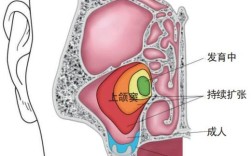

- CBCT (锥形束CT): 微创拔除的“金标准”,提供三维立体影像,精确显示:

- 多生牙的牙冠、牙根形态(弯曲、分叉)。

- 多生牙在颌骨内的精确位置(唇侧/腭侧/牙槽嵴顶)。

- 与邻牙牙根的距离(是否有粘连、压迫)。

- 与重要解剖结构(上颌窦、下颌神经管)的距离。

- 骨质覆盖情况(需要去骨多少)。

- 为设计手术入路、去骨范围、分根策略提供精确依据。